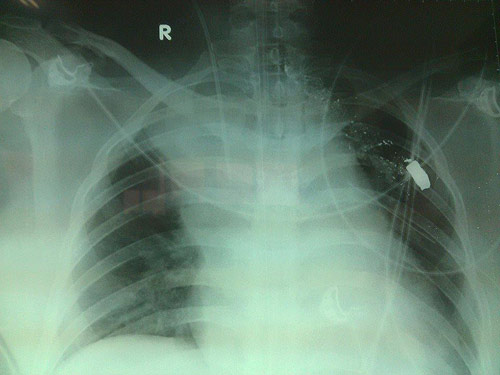

Đường đi của viên đạn và viên đạn trong người bệnh nhân khi bị bắn

Ngay sau khi tiếp nhận bệnh nhân, các bác sĩ Bệnh viện Việt Đức đã nhanh chóng tiến hành hồi sức bệnh nhân, hiện tại bệnh nhân đang bị sốc nhiễm trùng nặng, phải nằm thở máy cố định một chỗ nên chưa thể phẫu thuật lấy viên đạn ra được.

Ngoài sốc nhiễm trùng, bệnh nhân còn bị tổn thương phổi nặng, phải điều trị nhằm bảo vệ phổi. Đồng thời, các bác sĩ đang nghi ngờ vết thương của bệnh nhân ảnh hưởng đến dây thần kinh. Bởi, hiện tại hai chân của bệnh nhân không thể cử động được.